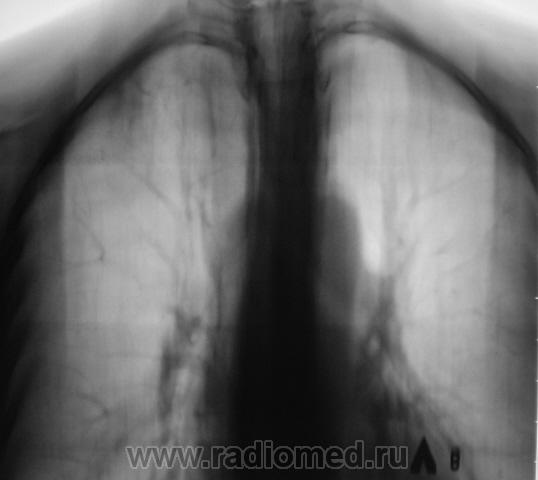

Пол пациента: Мужской пол Тип патологии: Инфекция Область исследования: Грудная клетка и верхние дыхательные пути Методы исследования: Rg После прохождения флюорографии взяли пациента на контроль, дообследовали и направили к коллегам-фтизиатрам. Пациент жалоб не предъявляет. Ваше мнение коллеги? Чт, 24/12/2009 - 14:18 #1 serega Не на сайте Был на сайте: 12 лет 4 месяцев назад Зарегистрирован: 15.10.2009 - 18:10 Публикации: 99 Здравствуйте, Валентин Львович. Тут по моему tbs. А почему Вы "боковушки" не наврезали? Или Вы посчитали, что и так всё ясно? Чт, 24/12/2009 - 14:26 #2 Катенёв Валенти... Не на сайте Был на сайте: 7 лет 3 недели назад Зарегистрирован: 22.03.2008 - 22:15 Публикации: 54876 Здравствуйте уважаемый serega ! Клиника типична - "клиники никакой", жалоб нет. Скиалогия также типичная, сомнений по поводу "очагового" не было. Выполнили "фтизиатрический стандарт" и отдали фтизиатрам.

Клиника типична - "клиники никакой", жалоб нет. Скиалогия также типичная, сомнений по поводу "очагового" не было. Выполнили "фтизиатрический стандарт" и отдали фтизиатрам.